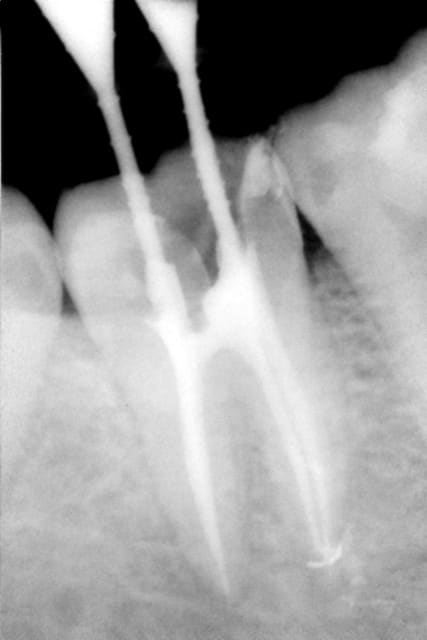

oui, c'était galère en plus. impossible de poser la digue, dent très délabrée et ouverture très limitée, pratiquement tout à la main, j'ai quand même fini avec le protaper rouge, je ne sais pas comment!!

Endo 47 bka74j - Eugenol

pour la 46, c'était plus simple, mais impossible de prendre les canaux mésiaux.

Endo 46 czlsam - Eugenol

ben pourquoi tu dis que t'es nul en endo mon biquet!

> oui, c'était galère en plus. impossible de poser

> la digue, dent très délabrée et ouverture très

> limitée, pratiquement tout à la main, j'ai quand

> même fini avec le protaper rouge, je ne sais pas

> comment!!

dans ces d'ouverture trés limitée, c'est là aussi où j'apprécie la rotation continue:

utilise les protaper en 21 mm et monté sur un CA avec une micro-tête de type AX endo (MM), trés pratique dans ce genre de cas. C'est bien plus facile que de faire tout à la main. :)